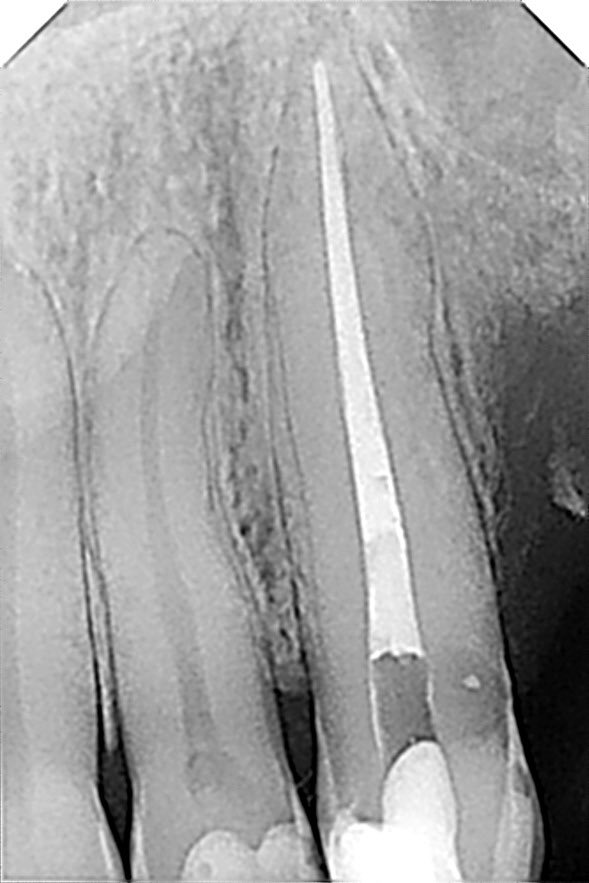

طبيب مقيم في علاج الجذور و عصب الأسنان 🦷 🦷 Endodontic resident at @ksmcmedia 📍Riyadh